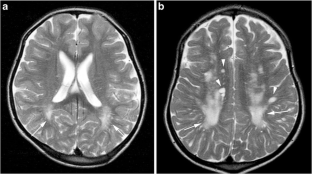

Fig. 2